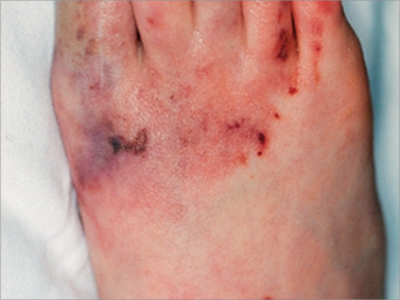

皮肤黏膜是艾滋病侵袭的主要部位之一,可表现为非感染性皮肤损害,皮肤损害呈多形性,可类似于脂溢性皮炎、鱼鳞病、毛发红糠疹、银屑病等,但症状一般更为严重。此外,还可出现特应性皮炎、光敏性皮炎、玫瑰糠疹、荨麻疹、多形性红斑及痤疮样皮损。

非感染性皮肤损害呈多形性,类似于脂溢性皮炎、鱼鳞病、毛发红糠疹、银屑病等,也可出现特应性皮炎、光敏性皮炎、玫瑰糠疹、荨麻疹、多形性红斑及痤疮样皮损。

多形性红斑样皮损表现为红斑、斑丘疹、水疱等,还可伴有瘙痒感、烧灼感;痤疮样皮损以粉刺、丘疹等为特征,随着皮损发展,可出现弥漫性红斑。